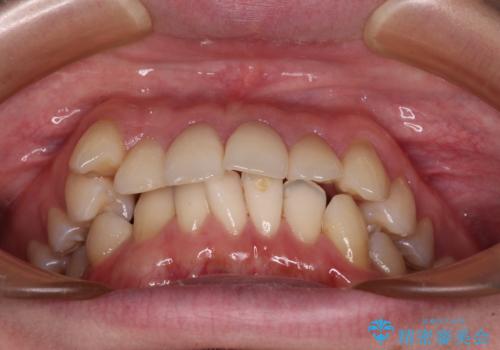

- 前歯のデコボコや八重歯を気にして来院された患者様です。

左右ともに奥歯の咬み合わせに問題があり、上顎臼歯が前方位にある状態で、結果として上顎前歯全体が前方位かつ叢生になっていました。

また、左右ともに上顎最後臼歯が頬側に転移していたため、補助装置を用いて舌側に移動をさせながら、上顎前歯を引っ込むように移動させることとしました。

口元の突出感を解消させるため上顎左右第一小臼歯2本を抜歯して、ワイヤー装置にて矯正治療を行うこととしました。